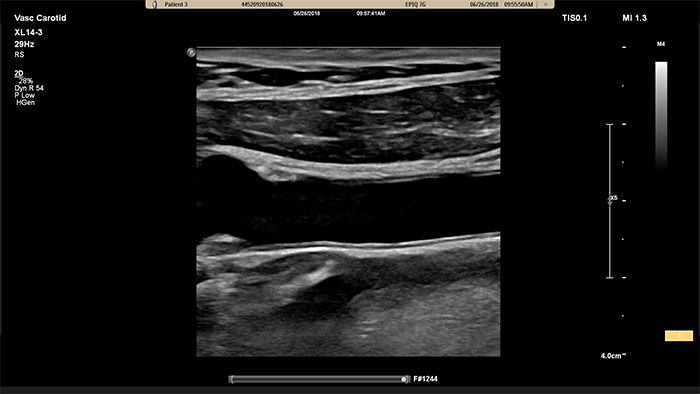

La sonde xMATRIX XL14-3 intègre 56 000 éléments remarquables, chacun connecté à un microcanal séparé. La sonde XL14-3 offre une focalisation électronique multidimensionnelle pour une imagerie échographique en coupes ultrafines de l’anatomie vasculaire et de la morphologie de plaque. Atout majeur : une fiabilité du diagnostic exceptionnelle lors de l’évaluation d’une sténose et d’une plaque vulnérable.